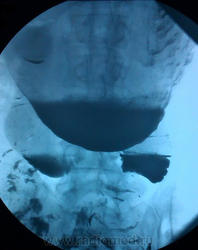

Мужчина, возраст в районе 50. Искали язву. За качество снимков извиняюсь, но сбросить на диск категорически не получается...

UPD: Первые 4 снимка сделаны в пределах 10 минут, последний - через 1,5 часа.

UPD 2: Пациент был проооперирован. Злокачественная опухоль тощей кишки, гистологию не уточняла. Честно скажу, что диагноз был поставлен не верно, правильный ответ всего лишь прозвучал в контексте: "не, ну не может же это рак быть". Основной теорией был АМК, ну и более популярные, чем рак, варианты, которые многие из вас отметили.

Желудок действительно странный. В просвете большое количество слизи. Или пациент нарушил подготовку, т.е. зубы почистил, выпил водички и т.д. Горизонтальная часть синуса и антрального отдела, как будто снизу чем -то подпирает. Складки сглажены. Признак артерио-мезентериальной компрессии есть, другое дело выражен он функционально. Данный АМК характерен не только истеричным женщинам, но и спокойным, а также и мужчинам. Тощая кишка расширена, и в ней тоже большое количество жидкости.

ИМХО: как уже сказали коллеги, расширение просвета тощей кишки, видимо по причине нарушения нормального пассажа, то же в 12-перстной кишке, можно преположить , что есть какая-то причина вне тощей кишки, например опухоль брюшной полости. Показано УЗИ органов брюшной полости. Компрессия 12-перстной кишки верхнебрызжеечной артерией есть, но это может быть конституционального характера, у худых. По методике исследования- все снимки сделаны в вертикальном положении, это не правильно- надо было посмотреть и в горизонтальном положении, многие вопросы ( в частности у нас) может быть и отпали бы. Вообще, это отдельная тема для разговора, говоря коротко можно резюмировать, что те рентгенологи которые пренебрегают этим правилом, пилят сук на котором сидят.

Частично барий начал проходить сразу, но полностью не ушел даже за сутки.